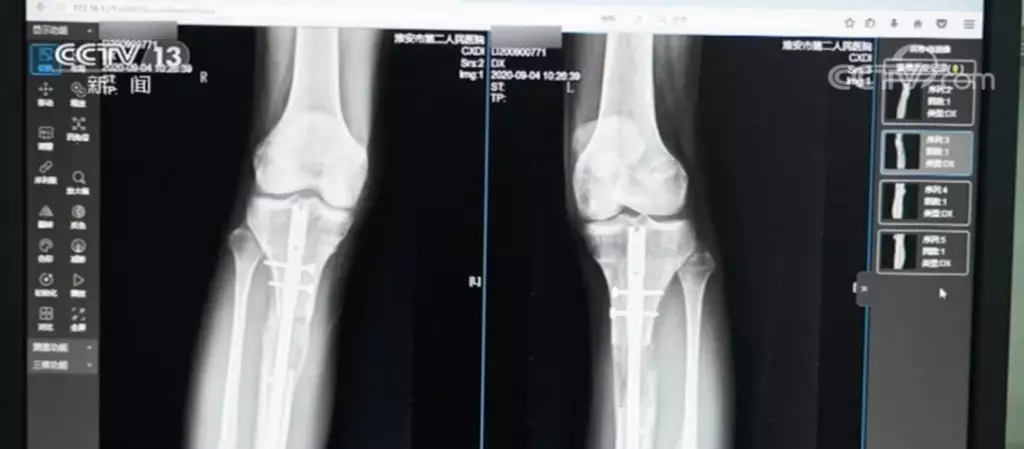

據淮安市第二人民醫院骨科主治醫師王磊介紹,這名男性患者22歲,當時是拄雙拐來就診的。通過拍X片發現,男子雙小腿做了增高手術,骨折斷端沒有完全癒合好,手術部位的皮膚有炎症反應。

患者自述今年5月在韓國做的「斷骨增高手術」,手術時,父母並不知情,目前仍不能獨立行走。醫生建議患者口服促進骨折癒合的藥物,適當增加負重鍛煉。如果三個月內仍然沒有骨癒合跡象,應該考慮施行自體骨移植手術治療。

「斷骨增高手術」又稱“肢體延長術”。骨科主治醫師王磊介紹,「斷骨增高手術」是根據肢體組織在一定的力量刺激下可以再生的原理,把小腿或大腿的骨頭“斷開”,然後在體外安裝具有牽伸作用的外固定支架,每天不超過1毫米的速度,將肢體緩慢延長到滿意的長度。